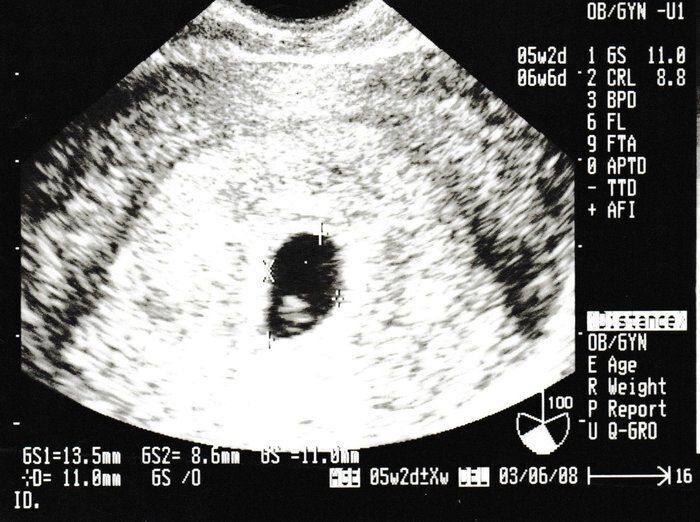

ママにエールさんの妊娠6週目のエコー写真

薄茶色のおりもの(出血)があり、気になって産院へ電話。「とりあえず、診察へ」と言われて受診しましたが、妊娠初期によくある程度の出血だから大丈夫とのこと。出血止めの薬だけ処方されました。ちょうどこの時、エコーで白い小さな粒を確認。「これが赤ちゃんに成長していきます」と先生に聞いて、愛しさでエコー写真をしばらく眺めていました。夫に見せたら、「ちっこい」と笑っていました。